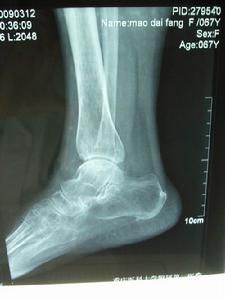

細胞、骨質細胞、髓質細胞(血管和神經)發生了壞死,致骨組織營養中斷或嚴重不足,使骨的代謝障礙,局部骨組織失去了營養,即為骨壞死。骨壞死原則上分為兩大類:一類是由於細菌感染所致的骨壞死,如:骨髓炎、骨結核、化膿性關節炎等。另一類是因缺血造成的骨壞死,如外傷、飲酒、激素藥、寒濕、肝腎虧虛、骨質疏鬆、扁平髖、脊髓異常空洞症等導致的骨壞死。人體任何部位都可能發生骨壞死,臨床以手舟骨、足舟骨、距骨、肱骨頭、肋骨、髕骨、鎖骨、股骨頭為多見,尤以股骨頭髮生率最高。骨壞死發生在股骨頭部位,就叫股骨頭壞死。

是診斷該病最簡單、最實用的方法,但敏感性差,早期單憑X線片不易診斷。骨壞死早期表現為骨質正常或輕度疏鬆,也可出現病變區骨密度相對均勻增高現象,隨後可見負重區有楔狀硬化帶或骨組織囊性病灶形成,進一步出現與關節面平行的“新月狀透亮帶”,關節間隙增寬。最後出現軟骨下骨板及關節面塌陷,骨輪廓改變,階梯狀不連續,骨壓縮加重,同時髖臼關節面也受損,關節間隙狹窄、骨贅形成,整個關節呈現退行性關節炎改變。